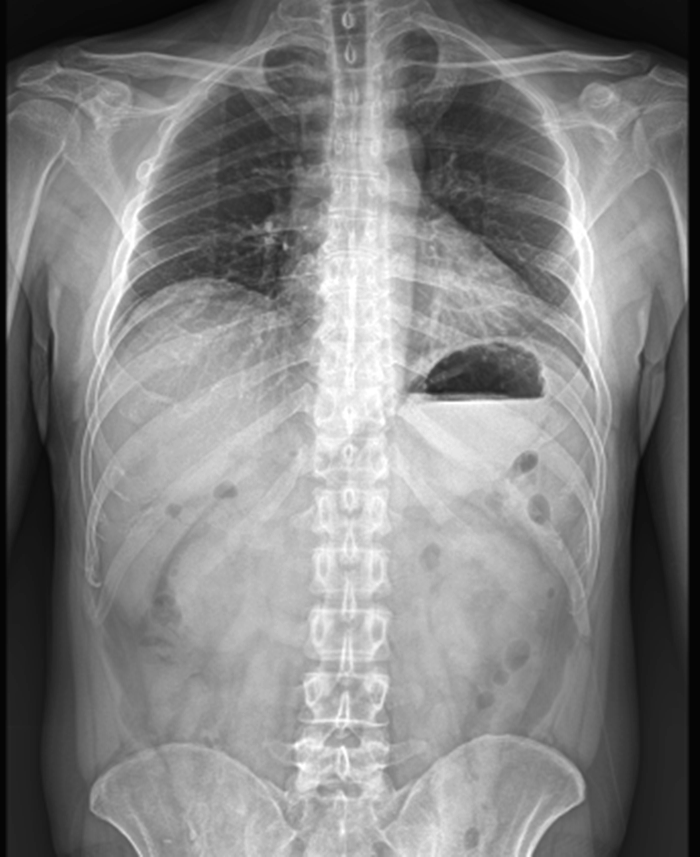

이 케이스의 경우에는 엑스레이상 척추도 바르고 어깨높이도 다르지 않습니다.

하지만 등고선을 보면 좌우가 다른것을 확인할 수 있죠. 우측 근육이 더 긴장하여 등고선이 높은 것을 확인해볼 수 있습니다.

그리고 쪽 등고선 역시 좌우가 다르다는 것을 확인해볼 수 있습니다.

이런경우 X-RAY 만 촬영했다면 아무 문제가 없다고 진단을 내릴 수도 있습니다.

이 사례 역시 위와 같은 상황입니다. 만성적인 허리통증을 호소하신 분인데 엑스레이에서는 척추도, 골반도, 어깨도 바른것으로 나왔는데 등고선은 좌우 차이가 보이시나요?

심지어 허리 중간쪽은 좌우가확연이 틀어진 것이 보이시나요?

이분은 허리쪽 근육이 과도하게 긴장해있어서 침을 맞을 때도 추나를 받을 때도 힘들어 하셨던 분입니다.

엑스레이를 여러차례 찍어봐도 아무 문제가 없다는 진단을 받았지만 통증때문에 너무 힘들었다고 하네요.

다른 치료방법이 없어서 도수치료를 받으며 겨우 참아왔다고 합니다.